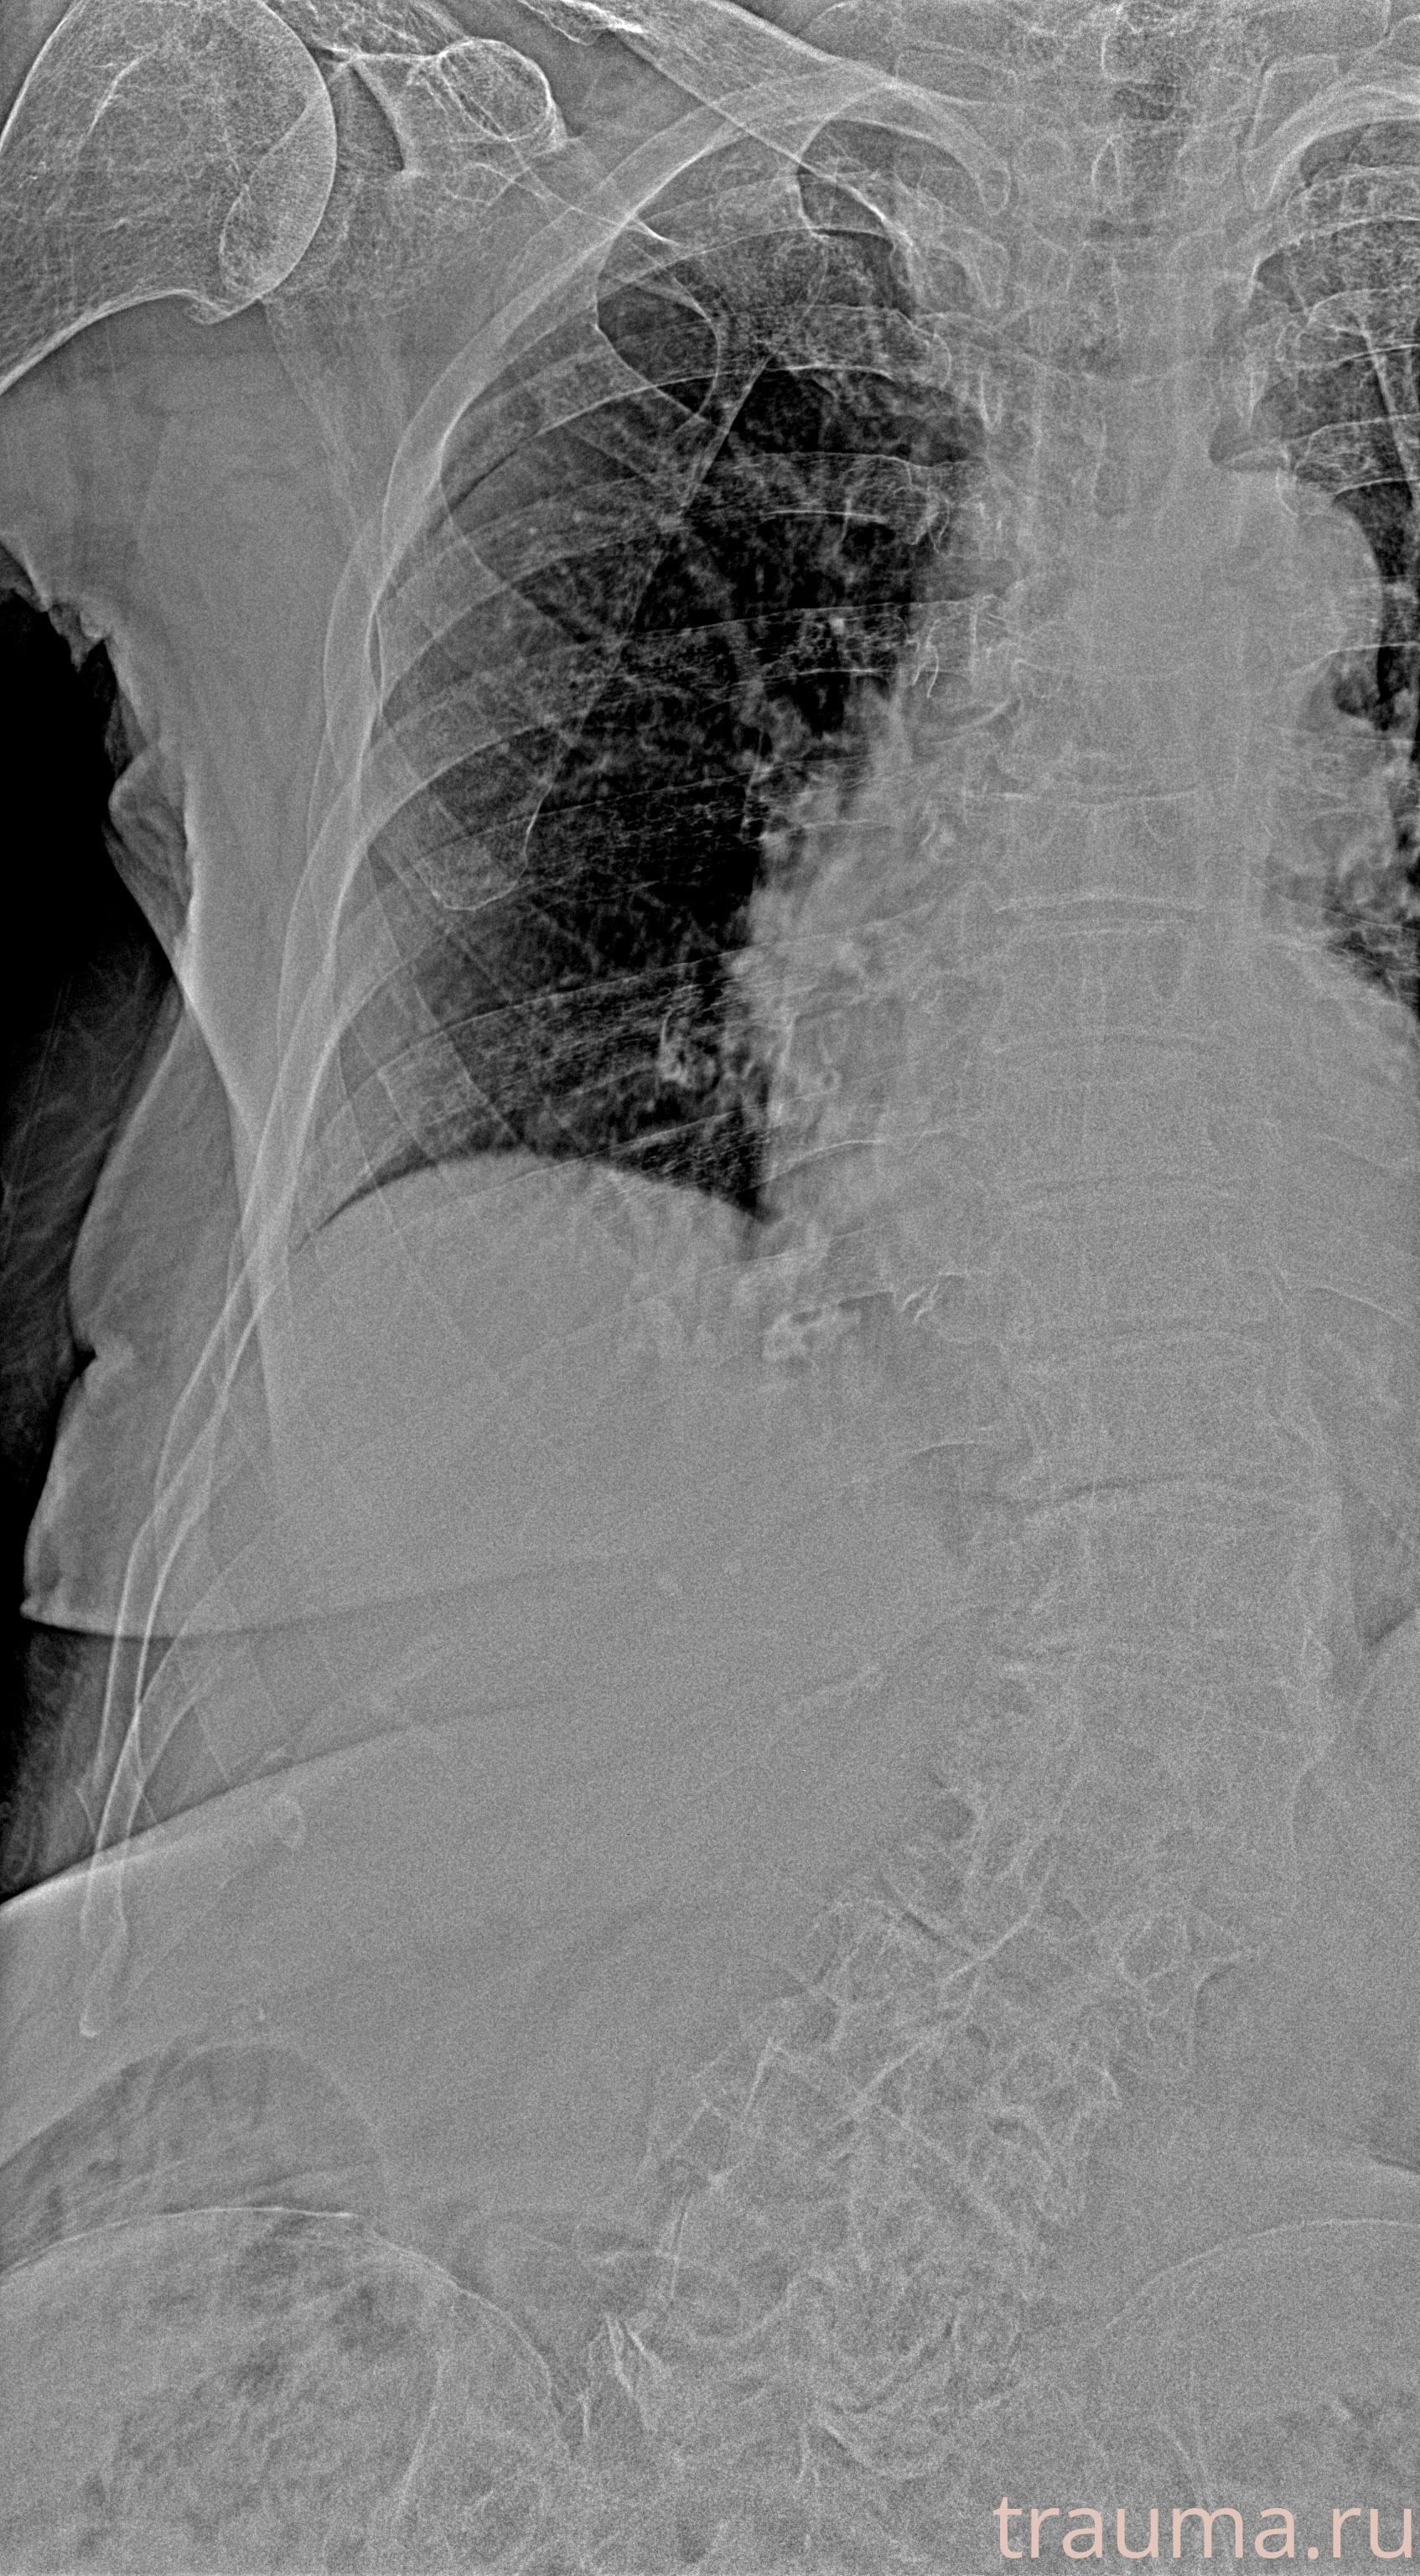

Рентген на дому: по вашему адресу приезжает врач-рентгенолог, травматолог-ортопед с мобильным рентгеновским аппаратом, проводит диагностику травмы или заболевания, делает необходимые рентгенограммы, дает рекомендации по дальнейшему лечению. Получить качественные снимки в домашних условиях возможно благодаря уникальной методике, разработанной МосРентген Центром для института  Склифосовского